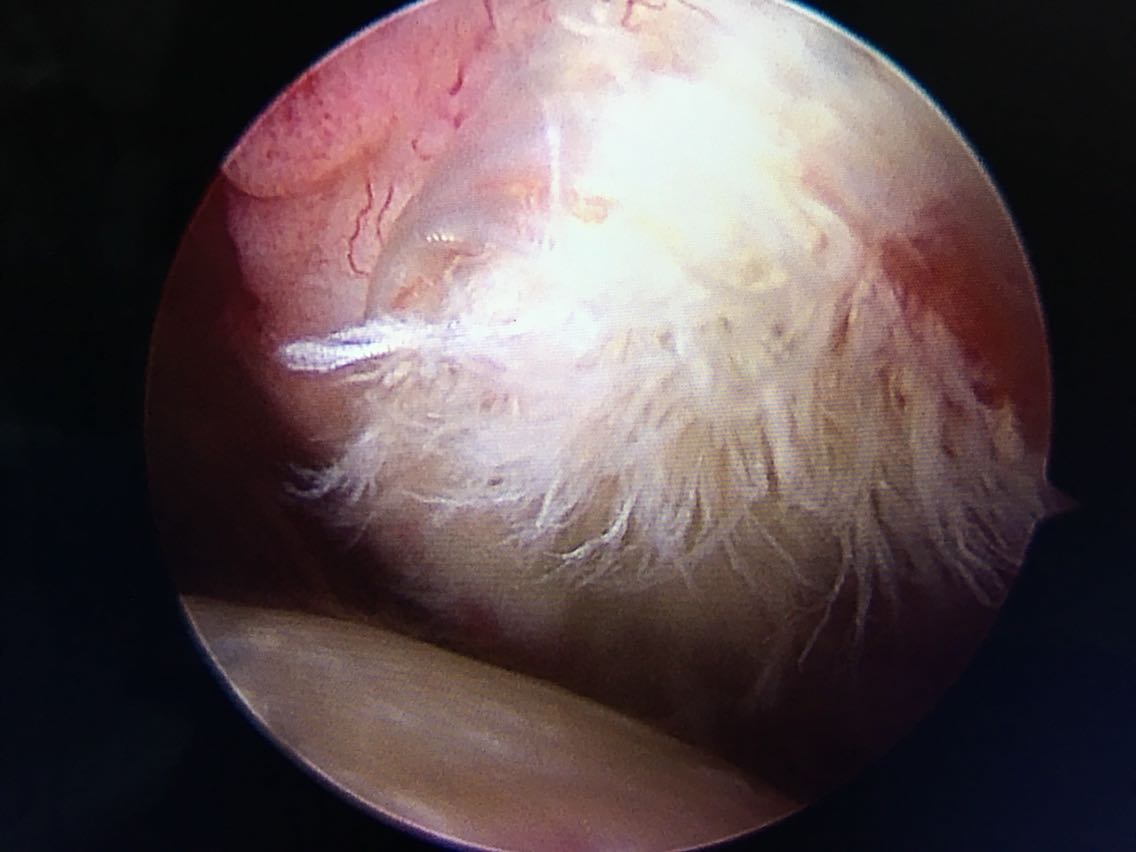

主诉:右肩关节疼痛、功能障碍6个月 现病史:患者于6个月前出现肩关节疼痛,以夜间明显,在当地医院诊断为肩周炎,给予指导关节功能锻炼,疼痛症状和功能障碍加重,效果不佳,来院就诊,核磁共振检查后,诊断为:肩袖撕裂 肩峰撞击症。收入院行关节镜下清理 肩峰成形 肩袖撕裂修补手术。

诊断:右肩袖撕裂 肩峰撞击症 冻结肩 治疗:关节镜下清理 肩峰撞击成形 肩袖撕裂修补手术。